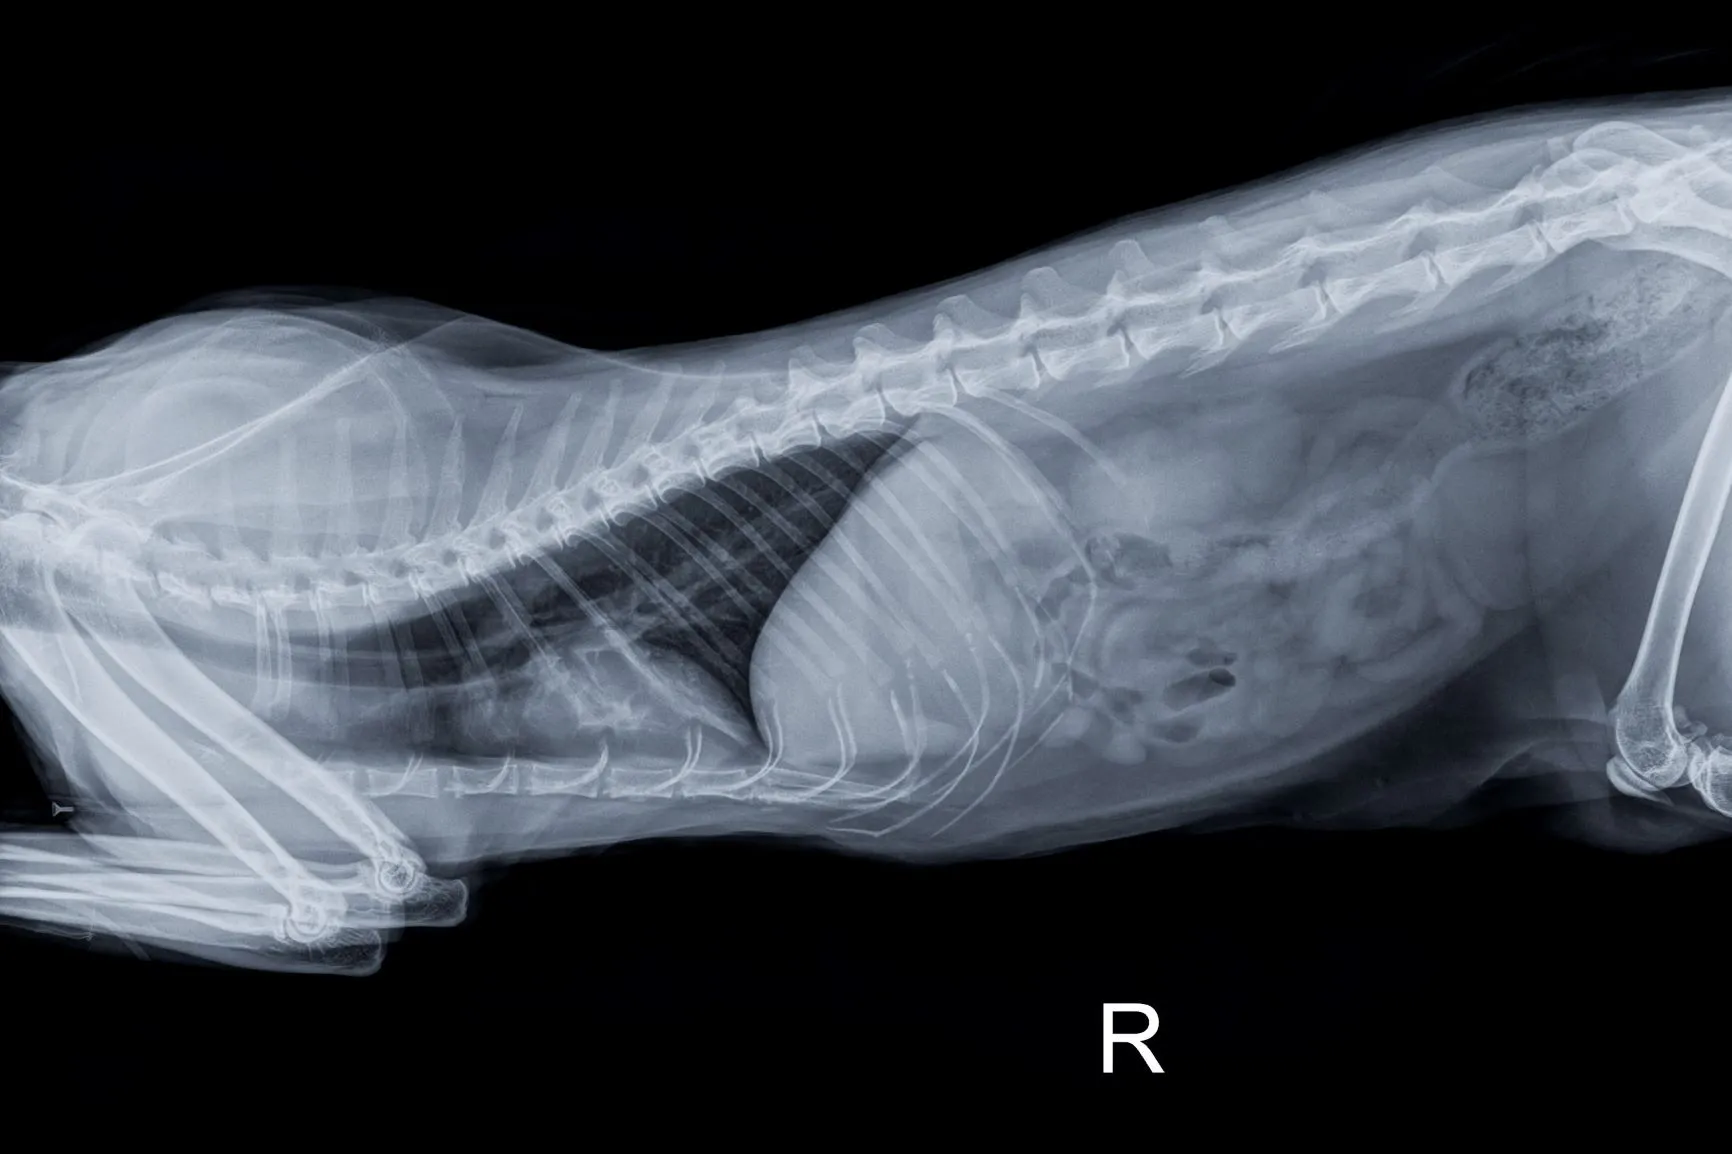

Knochen können durch angeborene Krankheiten oder eine Mangelernährung in frühen Jahren verändert sein. Häufiger kommt es jedoch dazu, dass sich Katzen die Knochen aufgrund eines Autounfalls oder heftiger Revierkämpfe brechen. Einen Knochenbruch können Tierärzte mit einer Röntgenuntersuchung sicher nachweisen.

Anatomie der Katze sichtbar auf einem Röntgenbild © Stefano Garau / stock.adobe.com

Ein Röntgenbild einer ausgewachsenen Katze